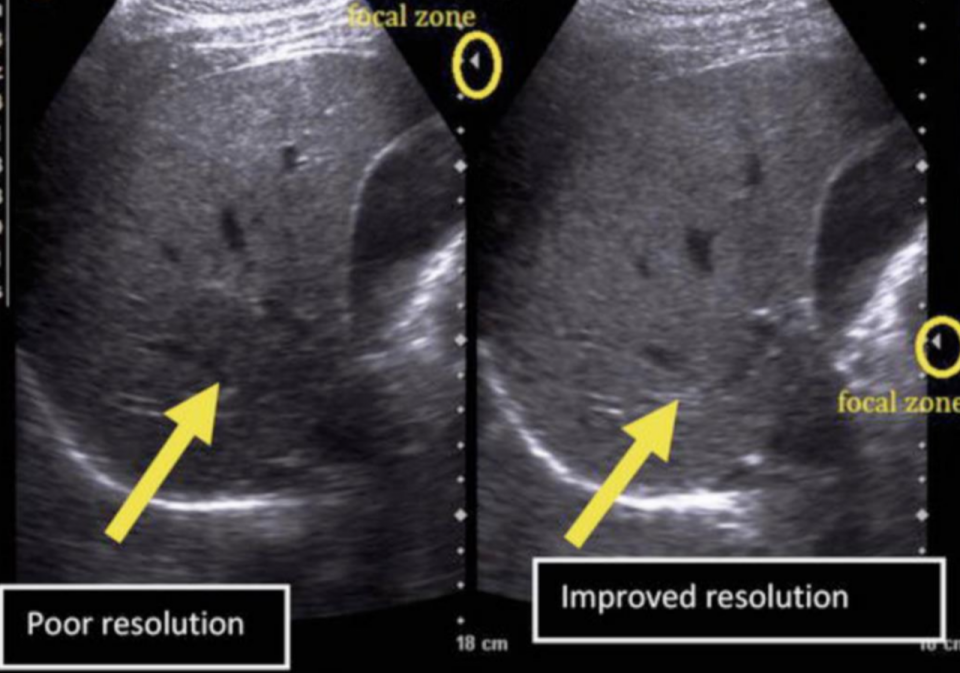

Focus Your POCUS

Rather than focusing on pathology, this article emphasizes the foundations of ultrasound image quality. It shows how deliberate probe handling, thoughtful optimization, and awareness of artifacts can turn inconsistent scans into reliable diagnostic tools.

Key teaching points:

-

Machine settings that truly impact image clarity

Structured probe movement and angulation techniques

Recognizing and correcting artifacts

When to pause, reset, and restart a scan

Documentation habits that support quality and learning